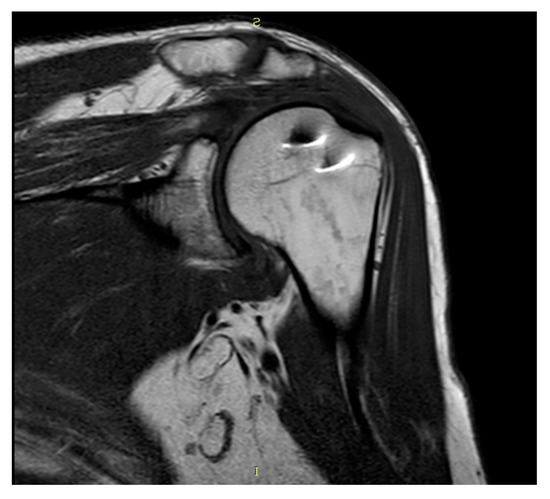

Plain radiographs and MRI showed coverage and centering of the humeral head, tendon continuity, and absence of fatty degeneration in all patients (Figure 3 and Figure 4).

Figure 3. Coronal T1-weighted MRI.

Figure 4. Coronal STIR-weighted MRI.